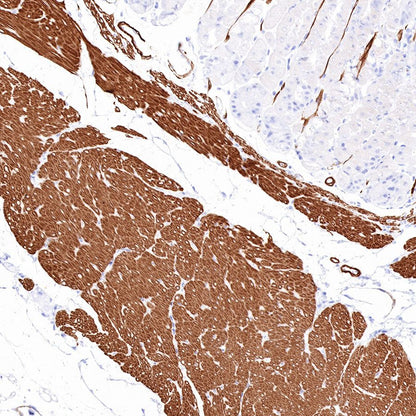

IHC shows positive staining in paraffin-embedded human colon. Anti-Smooth Muscle Myosin Heavy Chain (SMMHC) antibody was used at 1/1000 dilution, followed by a HRP Polymer for Mouse & Rabbit IgG (ready to use). Counterstained with hematoxylin. Heat mediated antigen retrieval with Tris/EDTA buffer pH9.0 was performed before commencing with IHC staining protocol.

IHC shows positive staining in paraffin-embedded human stomach. Anti-Smooth Muscle Myosin Heavy Chain (SMMHC) antibody was used at 1/1000 dilution, followed by a HRP Polymer for Mouse & Rabbit IgG (ready to use). Counterstained with hematoxylin. Heat mediated antigen retrieval with Tris/EDTA buffer pH9.0 was performed before commencing with IHC staining protocol.

IHC shows positive staining in paraffin-embedded human prostatic hyperplasia. Anti-Smooth Muscle Myosin Heavy Chain (SMMHC) antibody was used at 1/1000 dilution, followed by a HRP Polymer for Mouse & Rabbit IgG (ready to use). Counterstained with hematoxylin. Heat mediated antigen retrieval with Tris/EDTA buffer pH9.0 was performed before commencing with IHC staining protocol.

Negative control: IHC shows negative staining in paraffin-embedded human skeletal muscle. Anti-Smooth Muscle Myosin Heavy Chain (SMMHC) antibody was used at 1/1000 dilution, followed by a HRP Polymer for Mouse & Rabbit IgG (ready to use). Counterstained with hematoxylin. Heat mediated antigen retrieval with Tris/EDTA buffer pH9.0 was performed before commencing with IHC staining protocol.

IHC shows positive staining in paraffin-embedded mouse stomach. Anti-Smooth Muscle Myosin Heavy Chain (SMMHC) antibody was used at 1/1000 dilution, followed by a HRP Polymer for Mouse & Rabbit IgG (ready to use). Counterstained with hematoxylin. Heat mediated antigen retrieval with Tris/EDTA buffer pH9.0 was performed before commencing with IHC staining protocol.

IHC shows positive staining in paraffin-embedded rat colon. Anti-Smooth Muscle Myosin Heavy Chain (SMMHC) antibody was used at 1/1000 dilution, followed by a HRP Polymer for Mouse & Rabbit IgG (ready to use). Counterstained with hematoxylin. Heat mediated antigen retrieval with Tris/EDTA buffer pH9.0 was performed before commencing with IHC staining protocol.